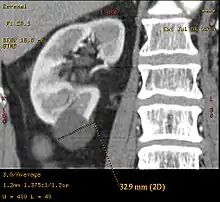

Category IIF

A Bosniak category IIF cyst. This one is 3 cm wide, with calcifications within its wall, seen as very radiodense (white in this presentation) areas in its margins. There is also a septation which is calcified. Yet, the cyst does not show enhancement (uptake of contrast).